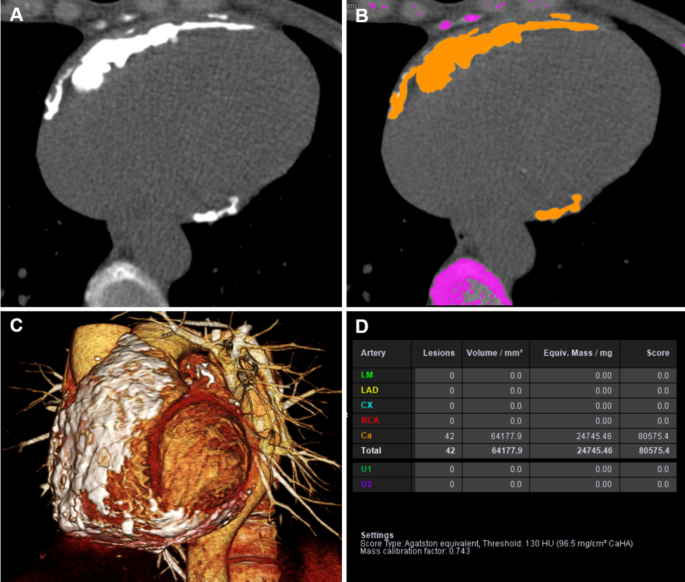

Image analysis

Calcium scoring CT images before pericardiectomy were analyzed using a commercial software to determine pericardial calcium volume and score, based on the Agatston score system (Syngo.via) (Fig. 3). Characteristics of pericardial thickening, including the presence of pericardial calcification, quantified volume and score of pericardial calcium, maximum pericardial thickness, maximum pericardial calcium thickness, and the presence of pericardial calcification adjacent to the major coronary arteries were evaluated on a PACS station. The presence of pericardial or pleural effusion was also recorded.

Quantification of pericardial calcium amount using the Agatston score method. (A) Cardiac gated calcium scoring image of the heart. (B) Pericardial calcium (orange color) selected by the software. (C) Three-dimensional volume rendering image of the heart indicating the extent of pericardial calcifications. (D) Results of quantified volume and score of pericardial calcium.